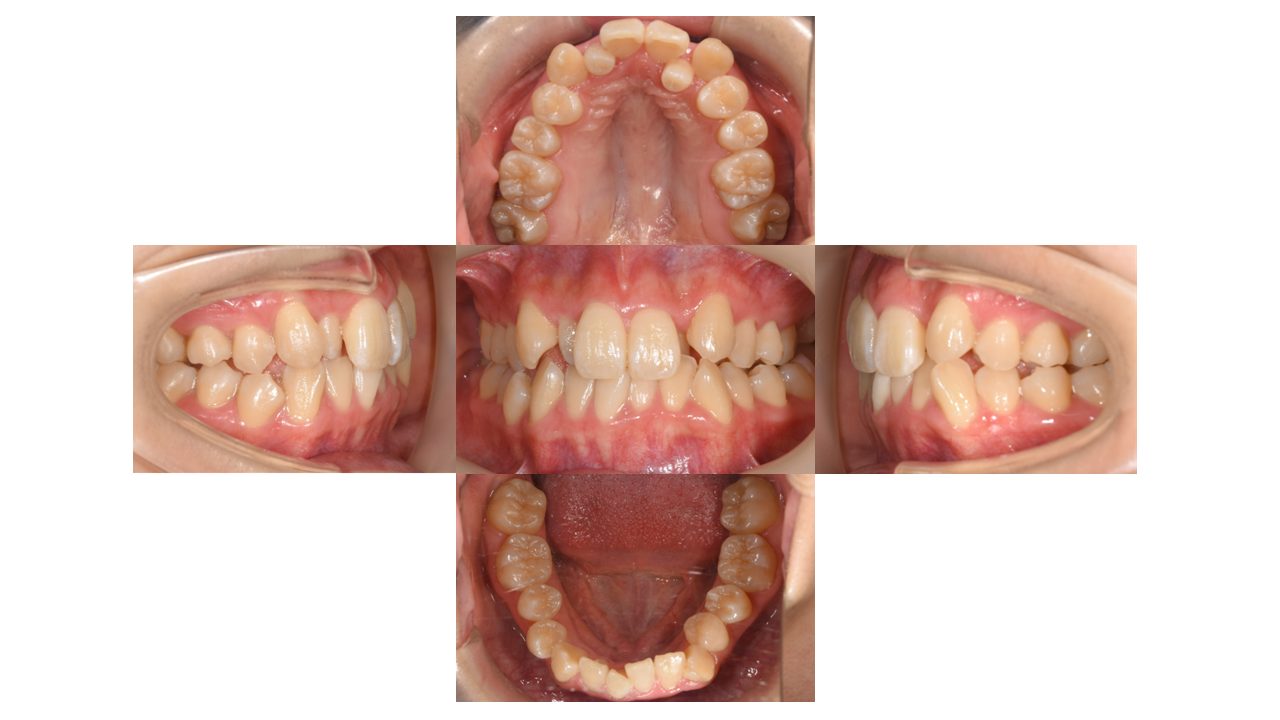

初診時の口腔内の状態です。

上下前歯の凸凹にお悩みでご来院されました。